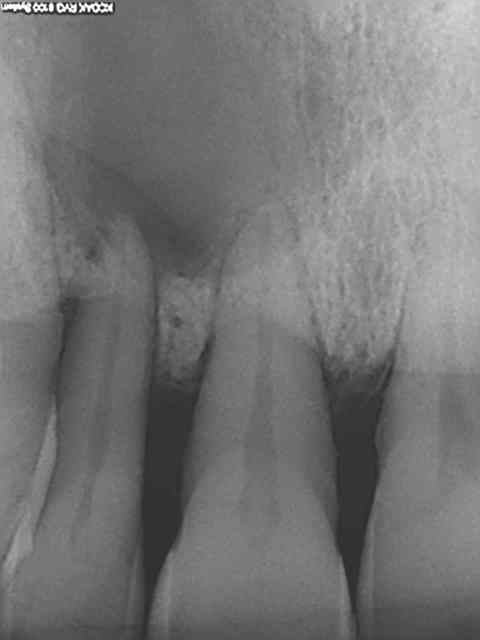

Tu as raison les panos c'est de la merde, mieux vaut faire des status rétroalvéolaires, z56, c'est plus précis. Et puis c'est pas de la médecine hein ? c'est que des chicots pas besoin d'examens complémentaires au pire c'est un quart d'une machoire qui se fait bouffer par un kyste. Je n'avais pas vu ce patient depuis 4 ans , pèche sur 12 asymptomatique. T'en penses quoi ? On attend que ca pète ? Et puis oui, tiens je vais pas faire en plus du chiffre en virant cette dent + curetage péri apical costaud pour la somme astronomique de 33,74 euros mon z56 me suffit,. En plus,si ca se trouve quand ca va arriver je serais en vacances.)))))))